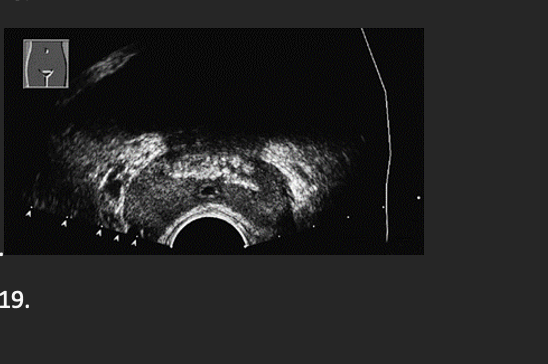

A patient presents with a history of hematuria and elevated prostate specific antigen(PSA). The neoplasm identified by the arrows is located in which region of the prostate gland? –

D. Peripheral zone